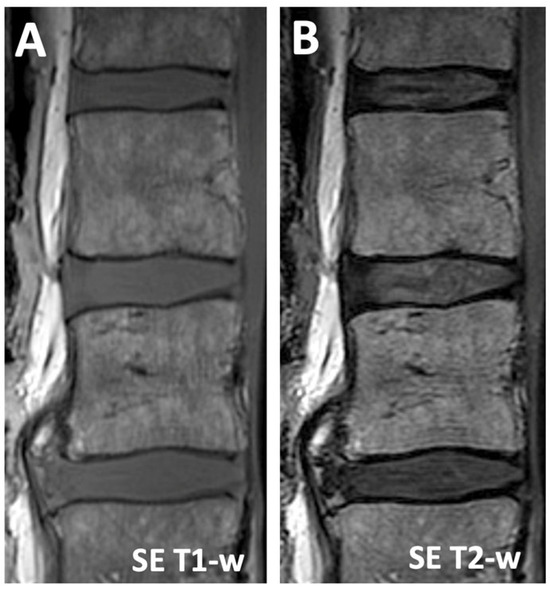

| 0.03 | 2.5 | 2.9 (0.7) | 1.0 (0.4) | 3.7 (1.1) | 1.8 (0.5) | −0.8 (0.6) | |

| 0.03 | 7 | 6.2 (1.5) | 2.6 (0.6) | 5.7 (1.3) | 3.6 (1.2) | 0.5 (1.3) | |

| 0.03 | 16 | 9.2 (2.4) | 4.7 (1.0) | 6.7 (1.6) | 4.5 (1.7) | 2.5 (1.4) | |